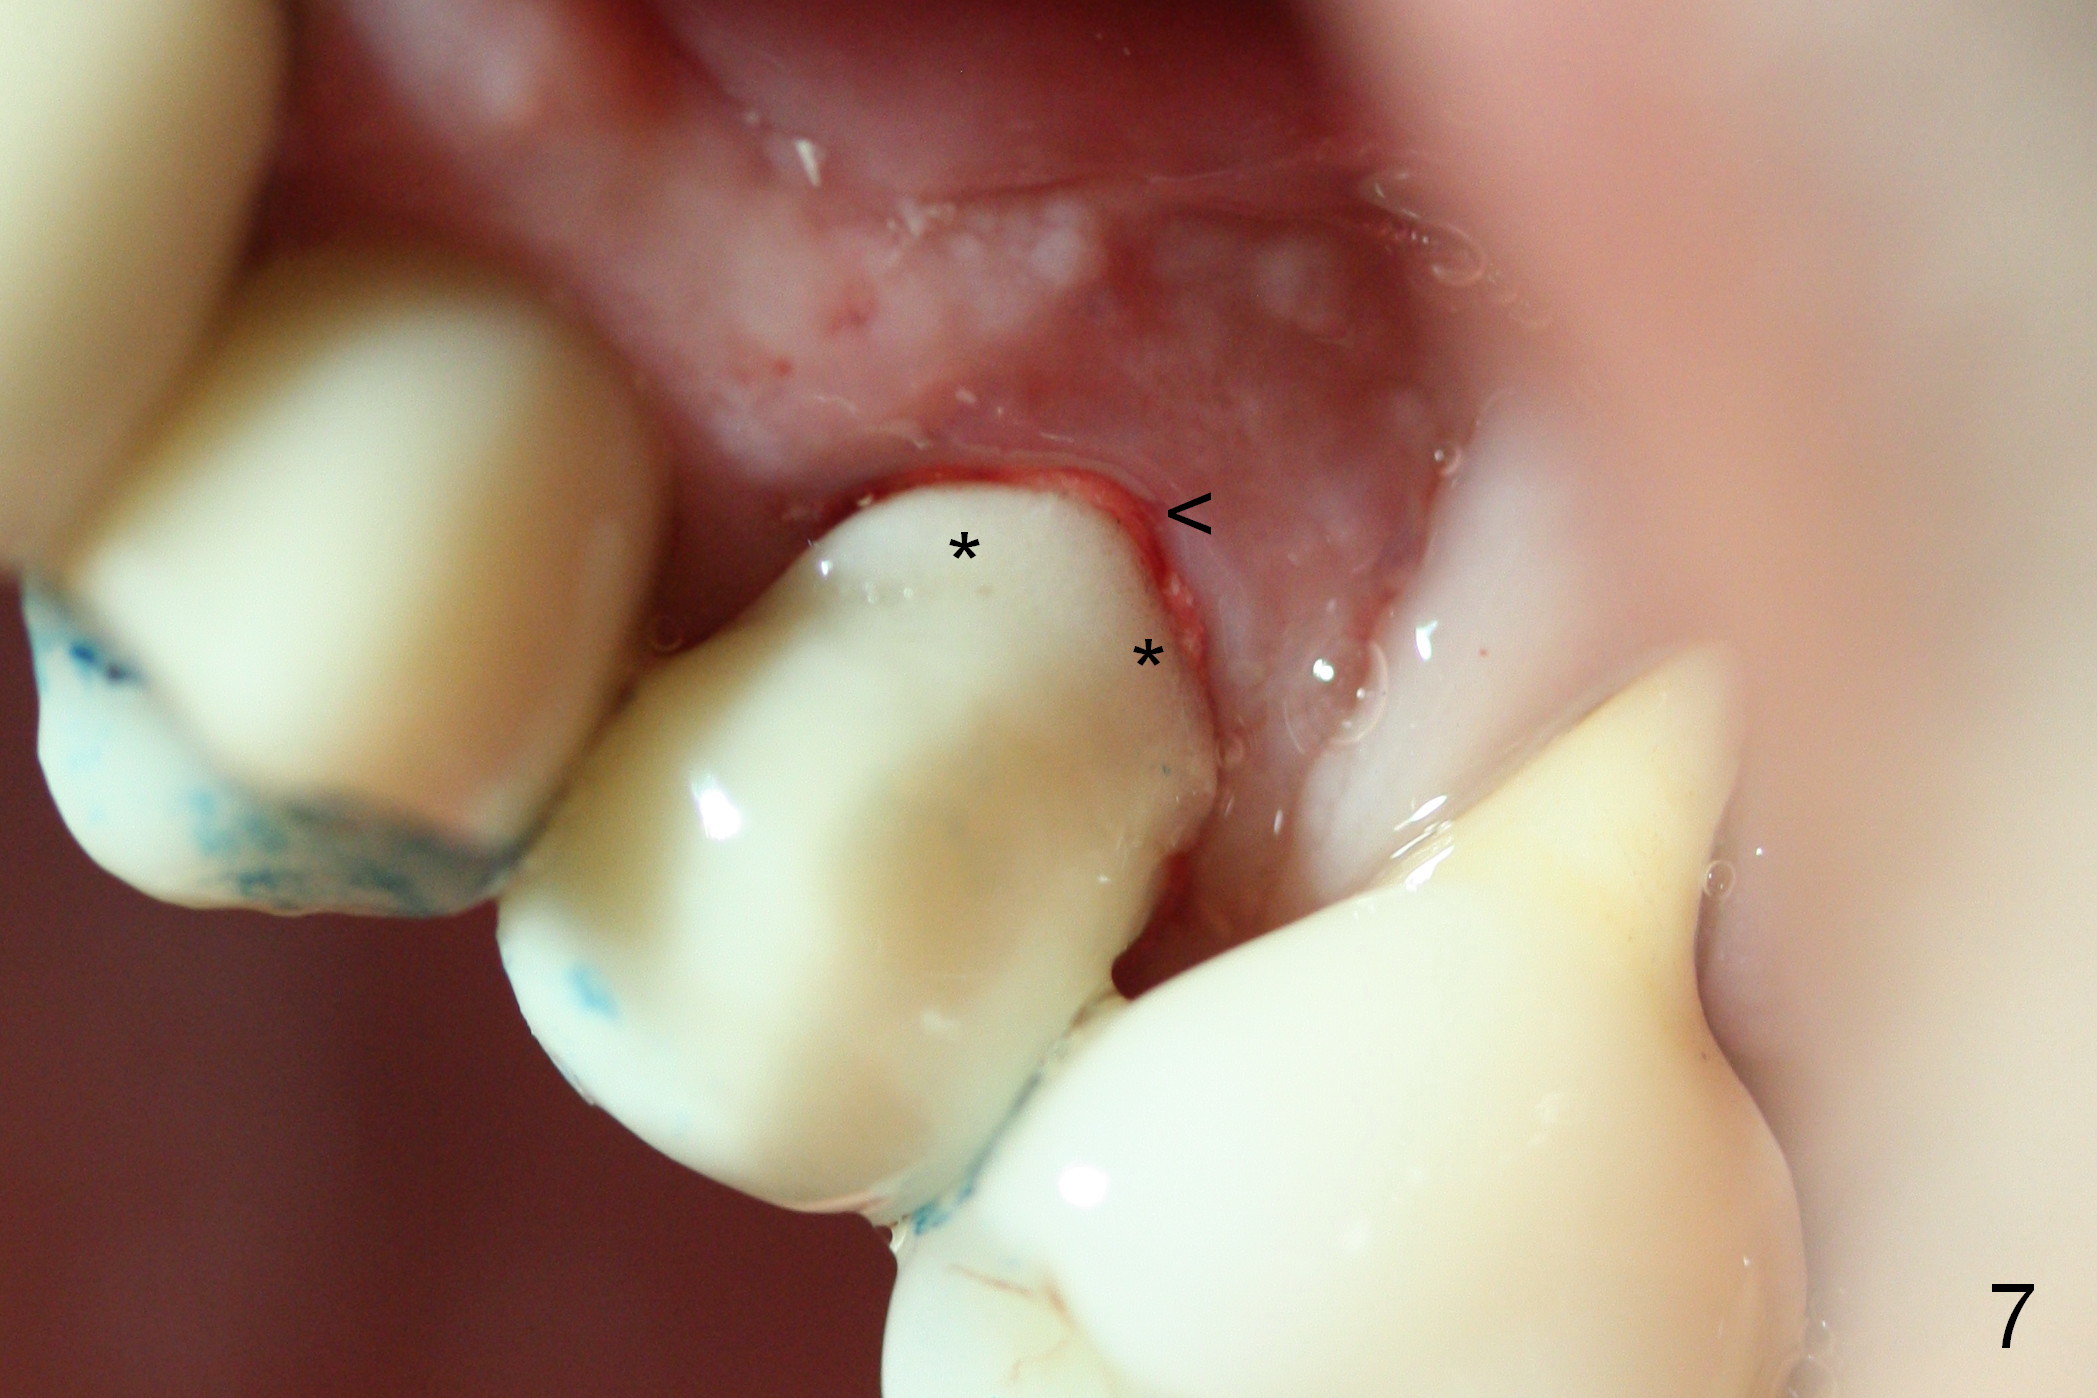

Extraction of the affected 2nd premolar is easy; the apical bone is so hard that drill and reamers have to be used for osteotomy, followed by insertion of a 4.5 mm tap with stability (Fig.1 T). The sinus floor (^) is lifted. There is no sign of sinus membrane perforation before placement of a 4.5x14 mm implant (Fig.2 I); sinus lift is performed (*: autogenous bone mixed with Mineralized Cancellous Human Allograft, Impladent); an immediate abutment (3.5x3 mm) is placed (A). With gauze placed in the buccal gap (Fig.3 G), the margin of the implant (I) is prepared for an immediate provisional fabrication. Mixture of autogenous bone (from reamers), allograft and Osteogen is placed in the remaining socket (Fig.4,5 *). When the relined (1st modification), trimmed and polished provisional is reseated (Fig.6 P), the bone graft (*) is not completely covered. New acrylic (2nd modification) is added to the margin of the provisional (Fig.7 *) for containment of the graft. There is almost no buccal plate; Osteotape (collagen membrane with Osteogen) is placed against the buccal wall of the socket prior to bone grafting. The remaining small pieces of the Osteotape (Fig.7 <) are laid over the bone graft before reseating the final provisional. With "complete socket seal", perio dressing is unnecessary.